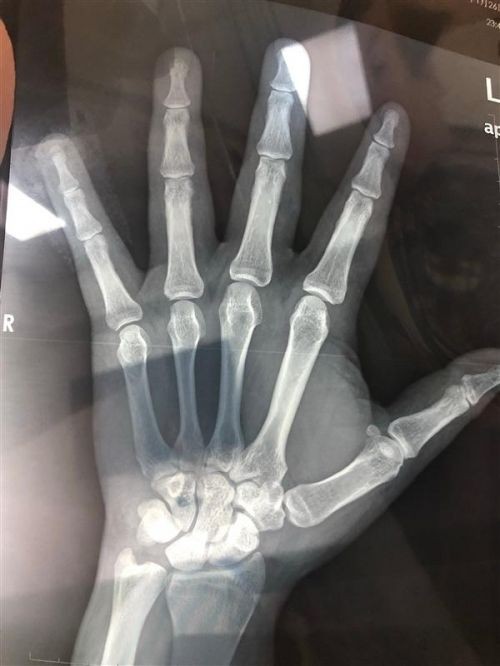

就在乘客害怕向后跑时,司机上车就开车跑掉了,乘客借助路人的手机才得以报警,后进医院治疗,左手无名指和小拇指被砍伤,左手小拇指骨头被砍断只有一小截肉连着了,如果恢复不好可能面临着截肢,十分痛苦。